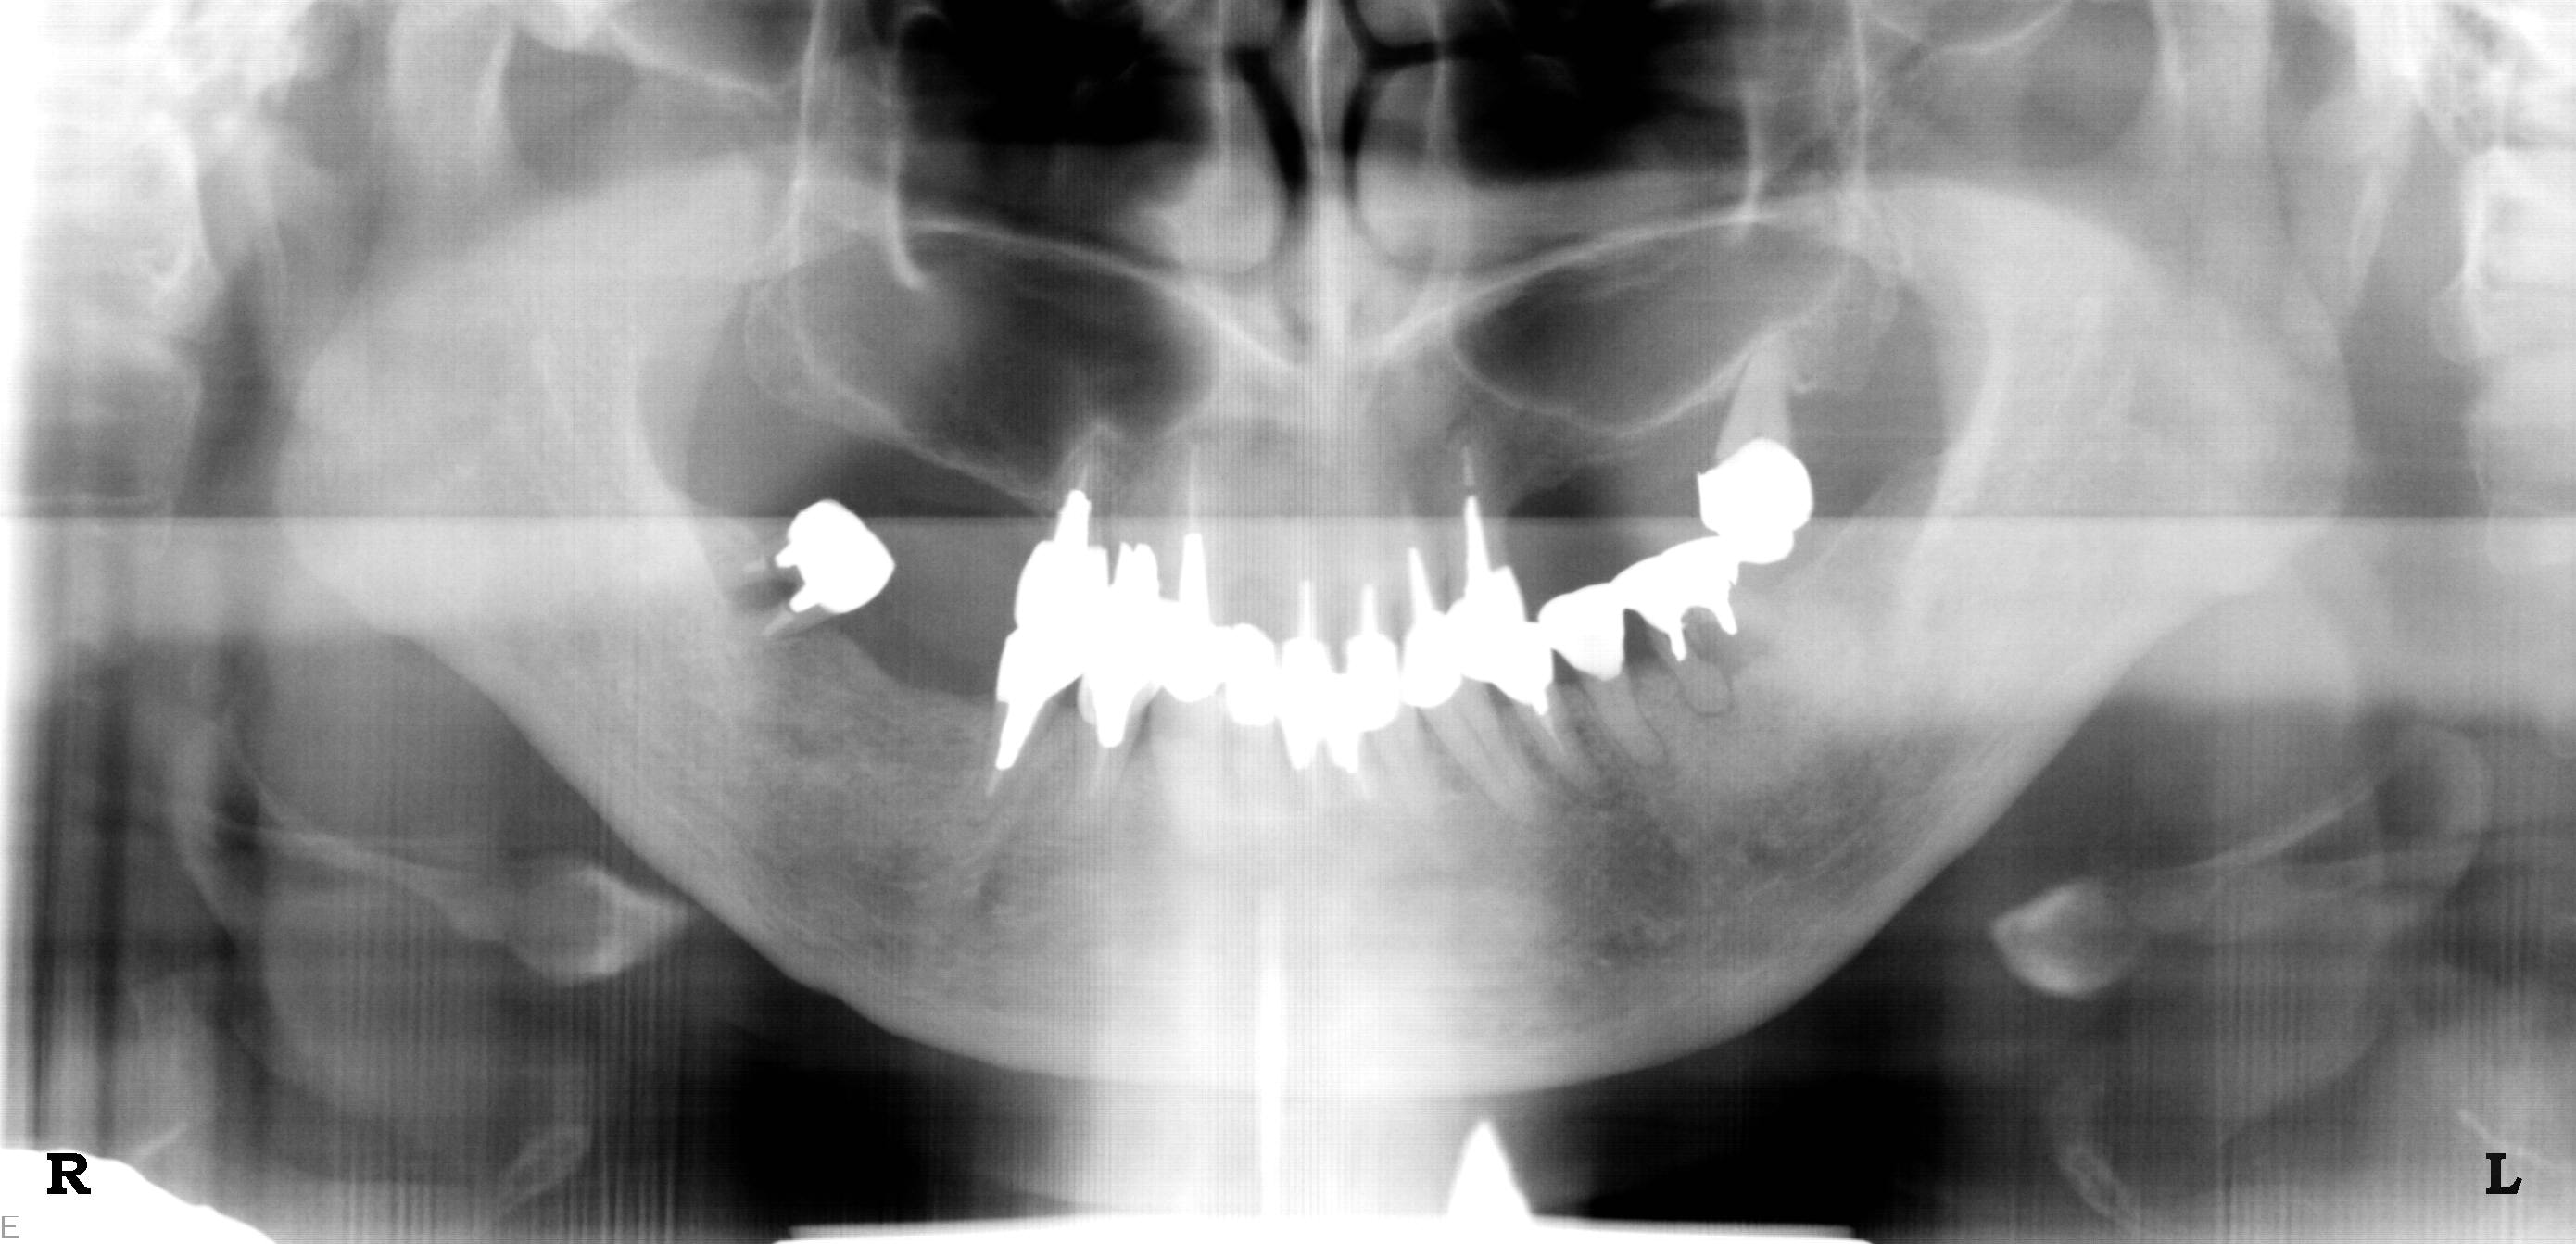

No.30HAコーティングインプラントを批判する方々へ